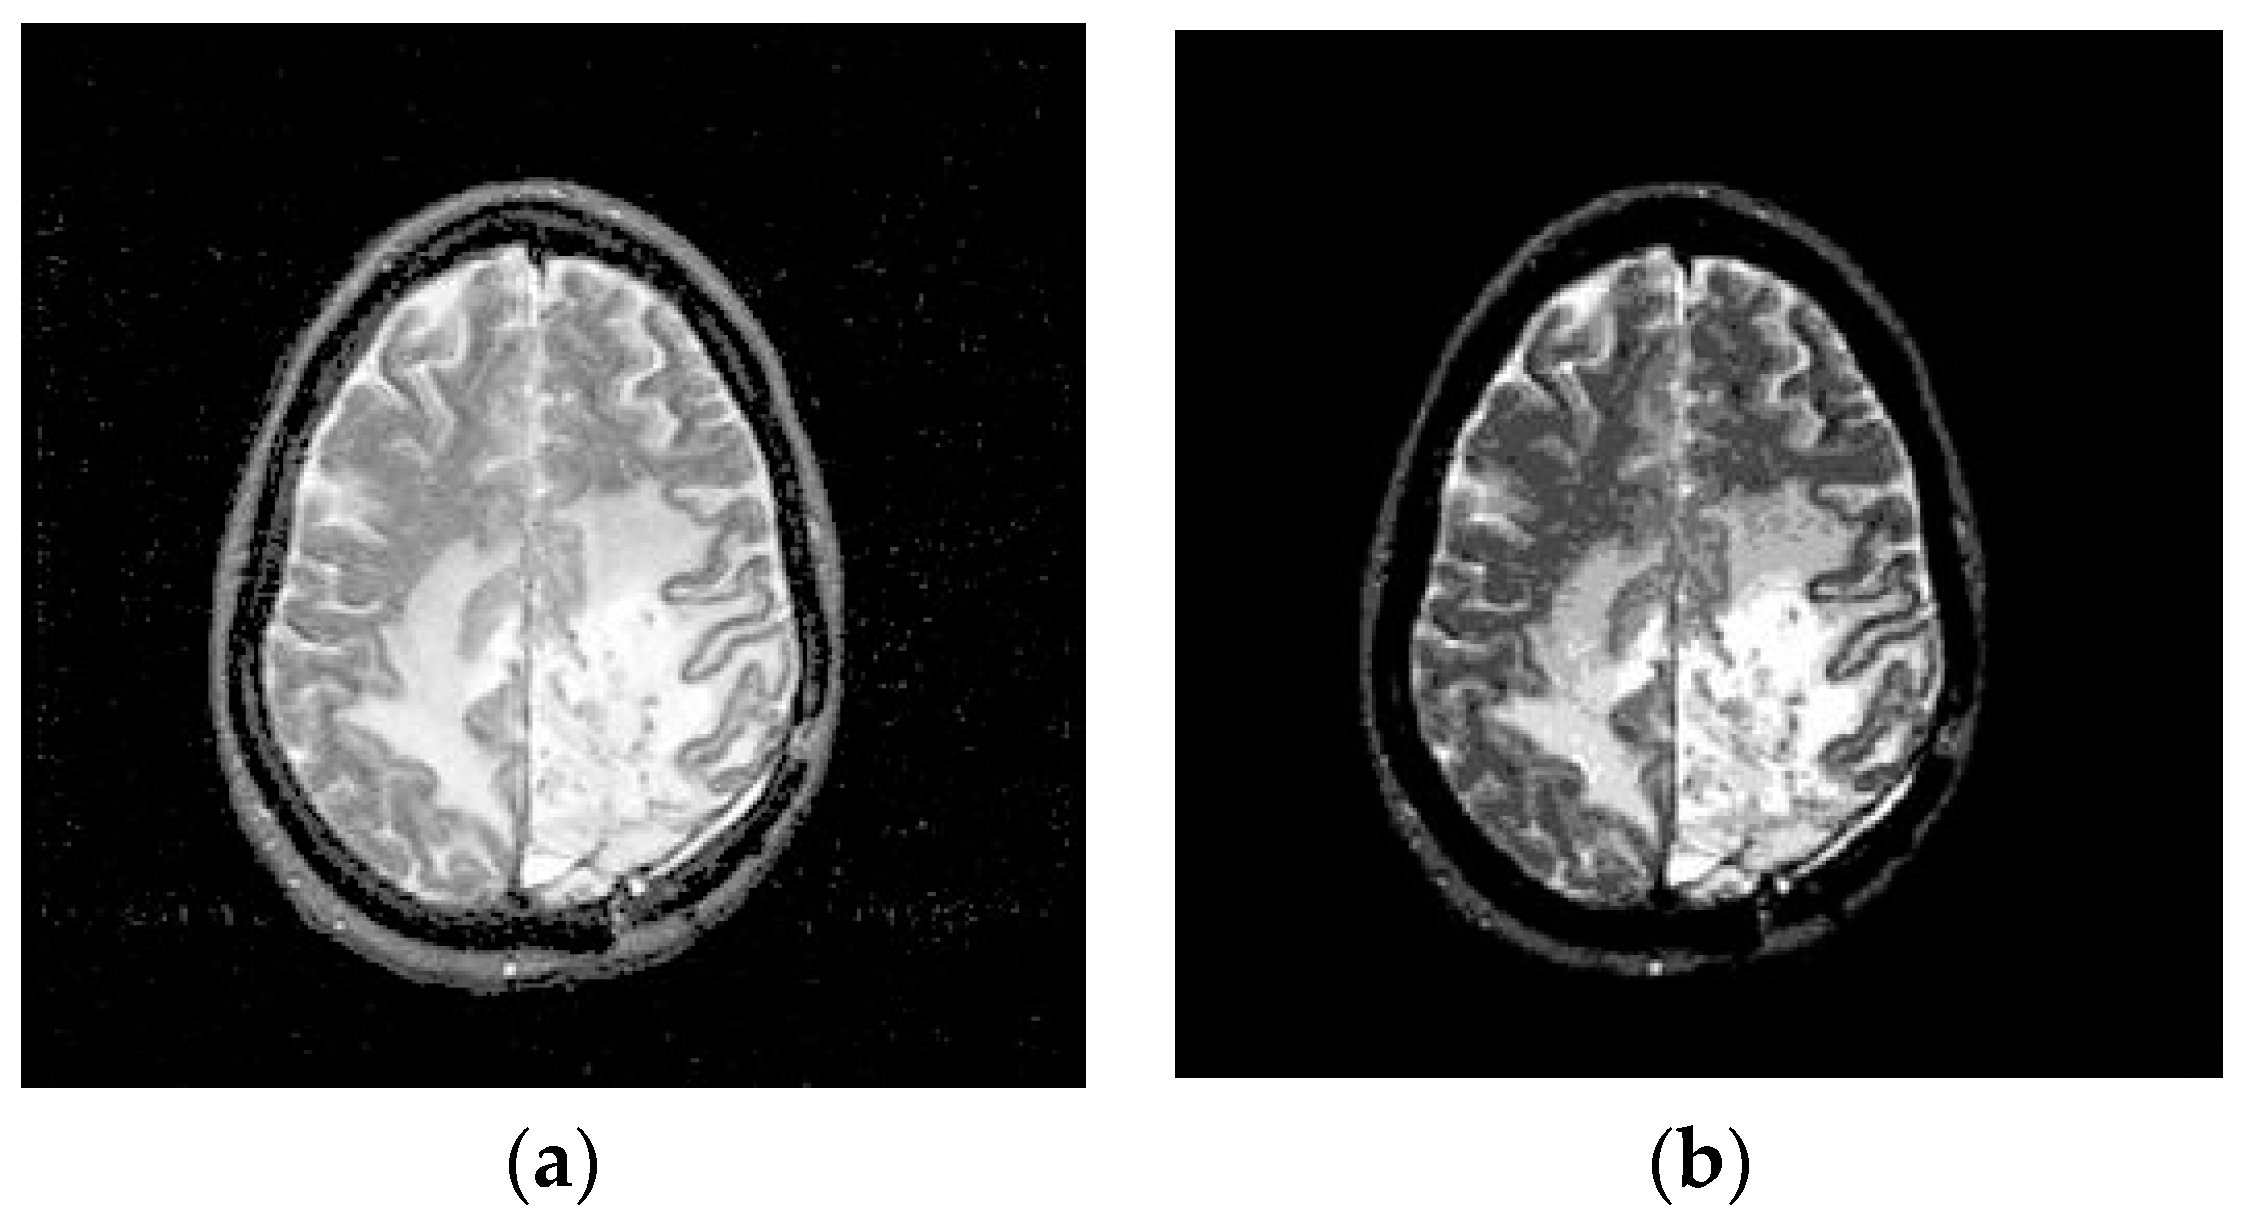

3.1. Preprocessing